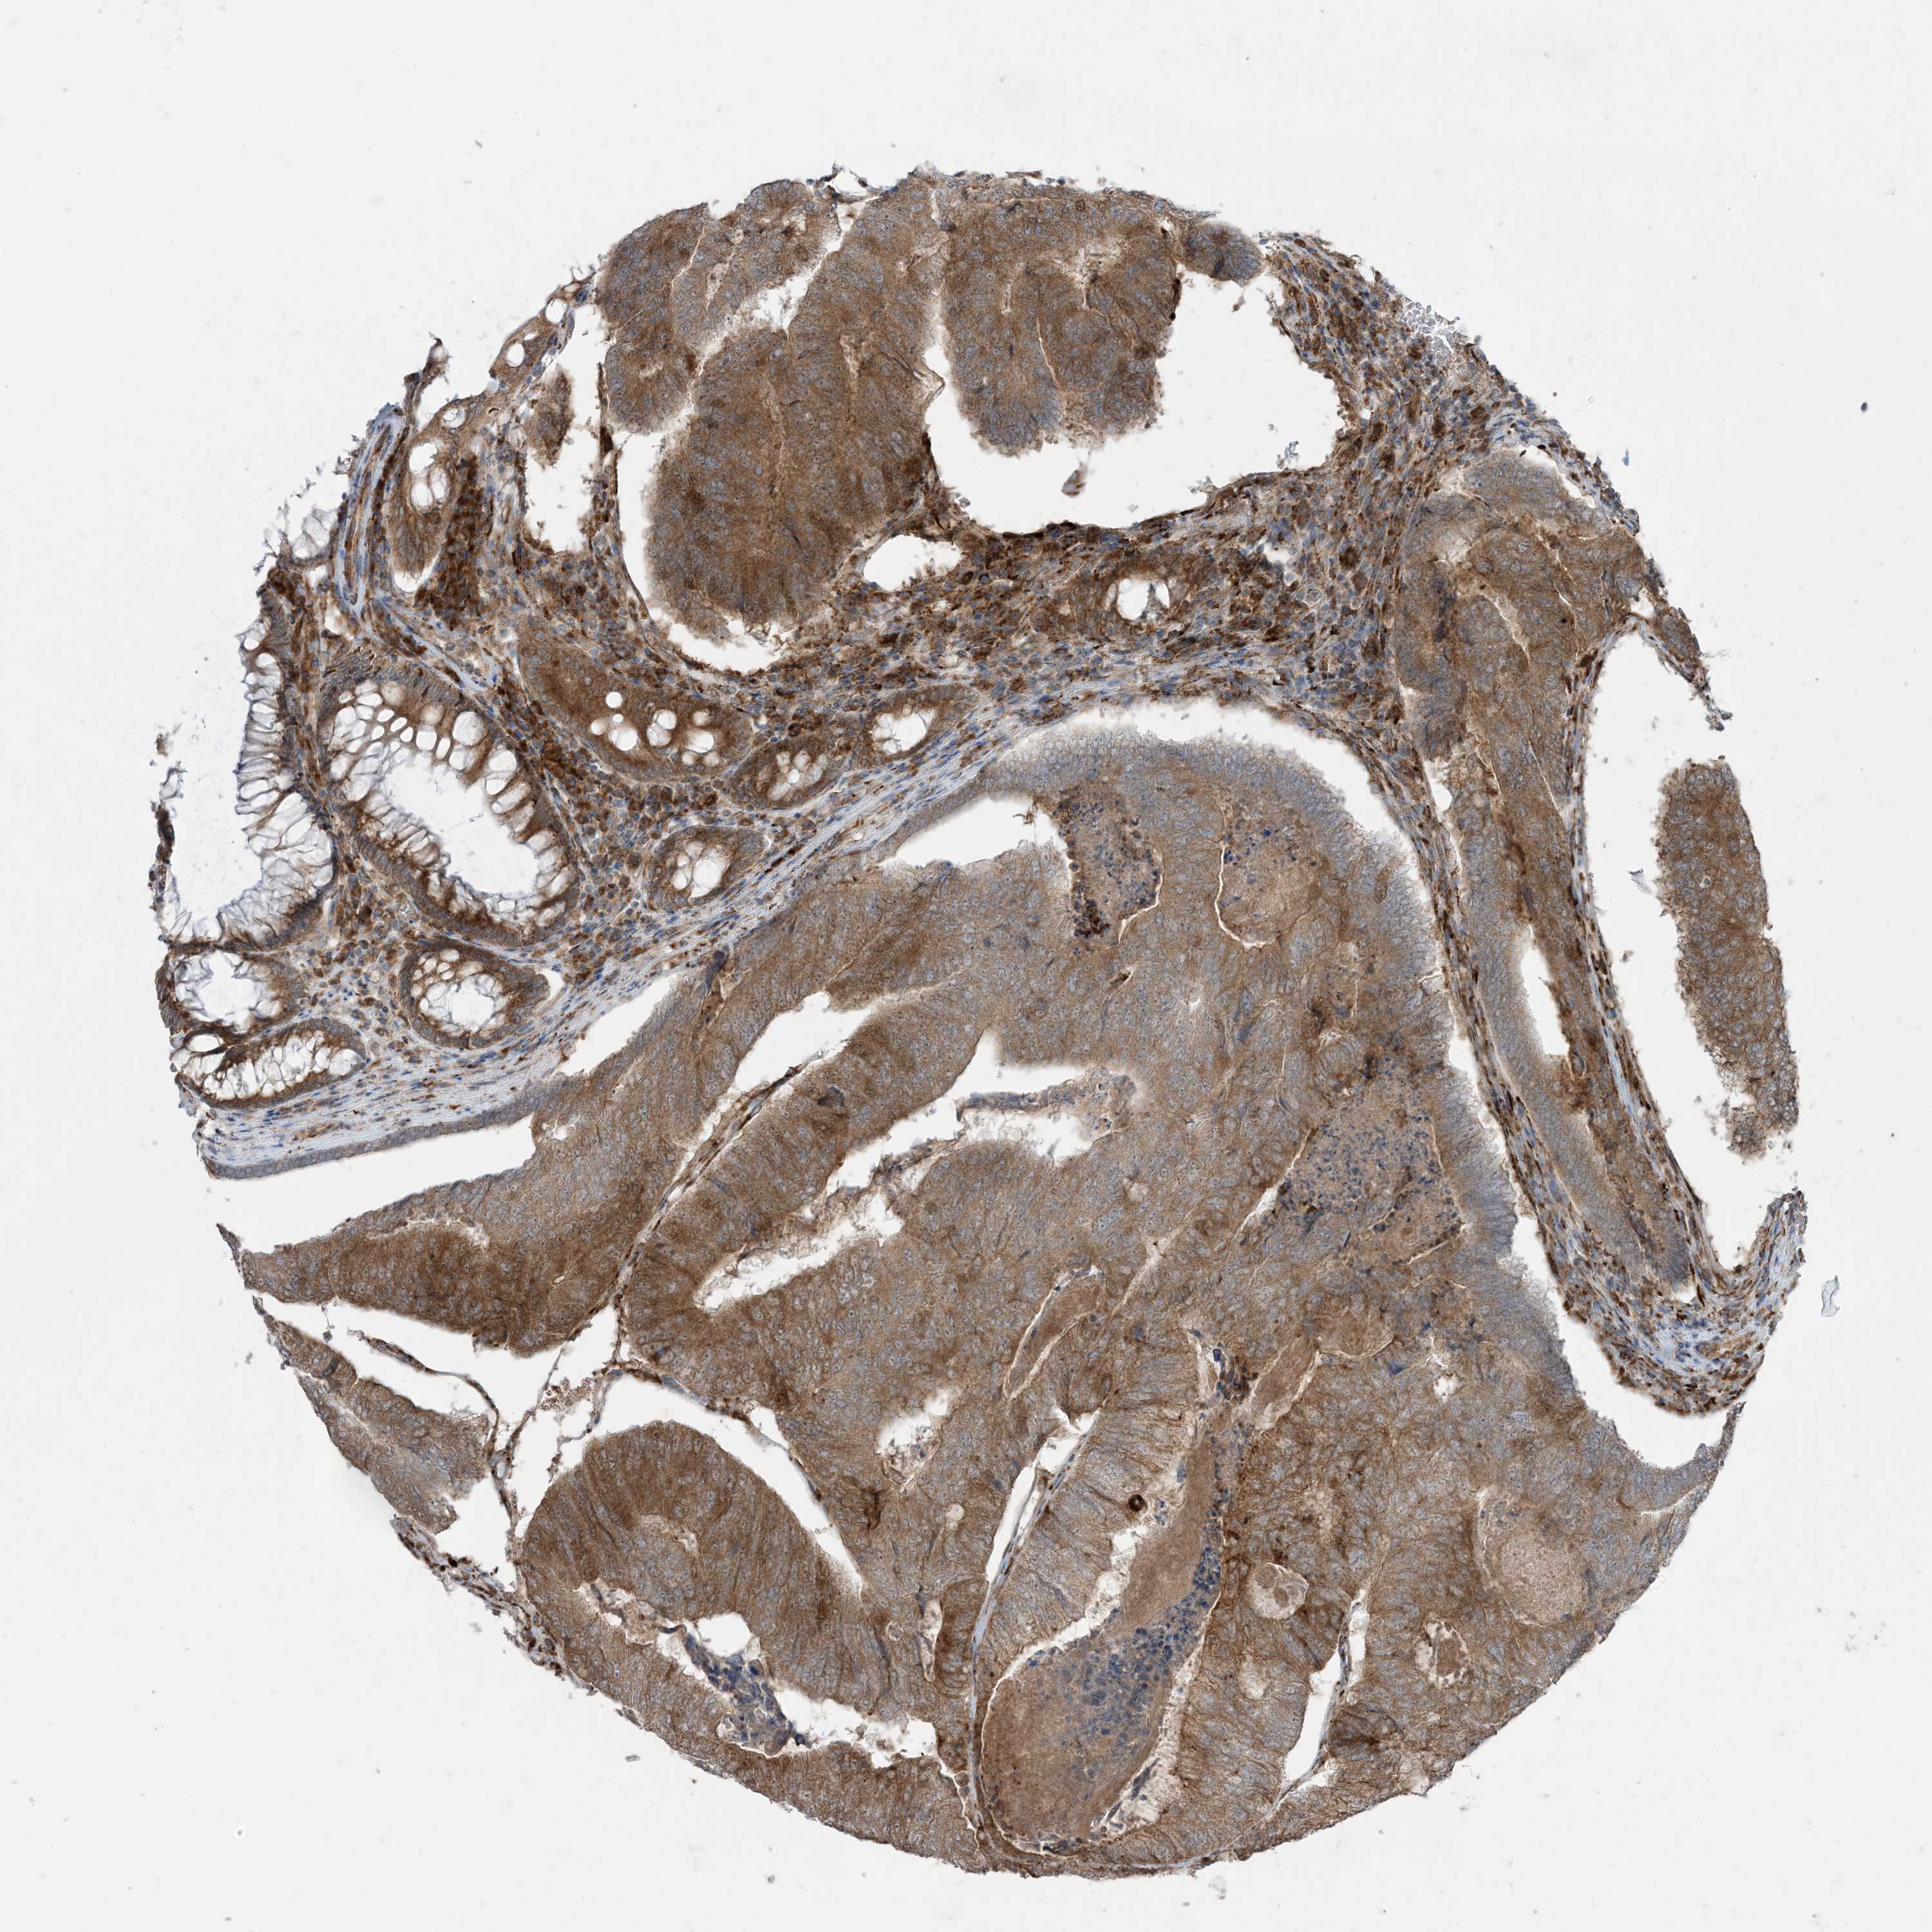

CANCER COLORECTAL CANCER Show tissue menu

Colorectal cancer

Human cancer

Colon adenocarcinoma